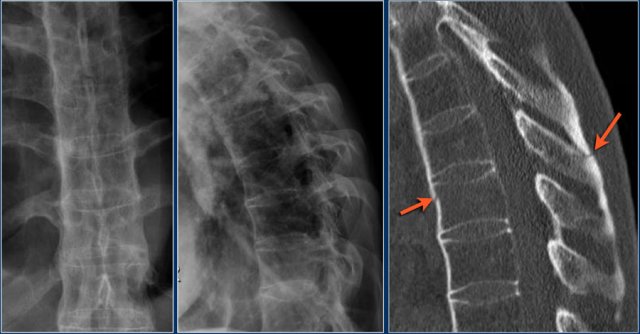

The images are of a patient with a typical bamboo spine as a result of ankylosing spondylitis.

After a fall on his back no fracture was seen on the x-rays.

However the CT shows a thin fracture line through the anterior side of the vertebral body and also through the spinous process.

Continue with the MR-images.

Look at the images.

What are the findings?

Then scroll to the next images.

The findings are:

1. Vertebral bodies show marrow edema as a result of a fracture.

2. Torn flaval ligament (yellow arrow).

3. Fractures through the posterior elements (red arrows).

The TLICS-score is high, because there is distraction and injury to the PLC.